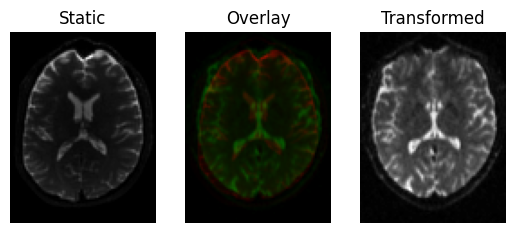

This results in a slight shear and scale

Registration result with an affine transform, using Mutual Information.